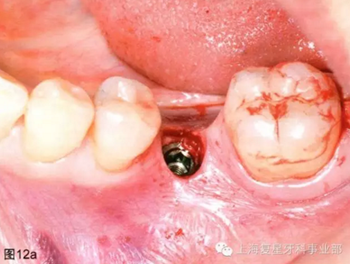

通過導(dǎo)板的引導(dǎo),以15prm,50Ncm旋入種植體。一旦種植體到達(dá)最后的深度(圖12a),去除種植手機(jī)和攜帶器,然后將一個(gè)愈合基臺(tái)(BioHorizons,直徑4.5毫米×長3毫米)擰在種植體上(圖12b)。軟組織打孔器取出的軟組織進(jìn)行結(jié)締組織移植,然后放置在一個(gè)頰楔上獲得一定體積和厚度的角質(zhì)化軟組織(圖12c)。無需縫合。術(shù)后拍攝X片,對種植體的最終位置進(jìn)行評(píng)估。

圖12a:種植體放置最終的位置上